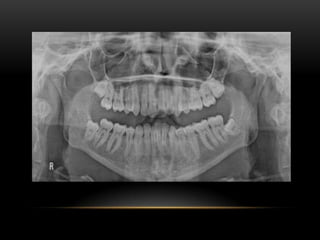

• It can be concluded that Oroantral communication is mainly caused by the extraction of

posterior teeth on the maxilla. If not treated the defect may become infected leading to

other health problems. Therefore, it is recommended that before any extraction of the

upper teeth is done the patient should be assessed carefully. A proper radiograph should

be taken to give a proper picture of the position of the teeth and if it is a possible OAC

then proper precautions should be taken.